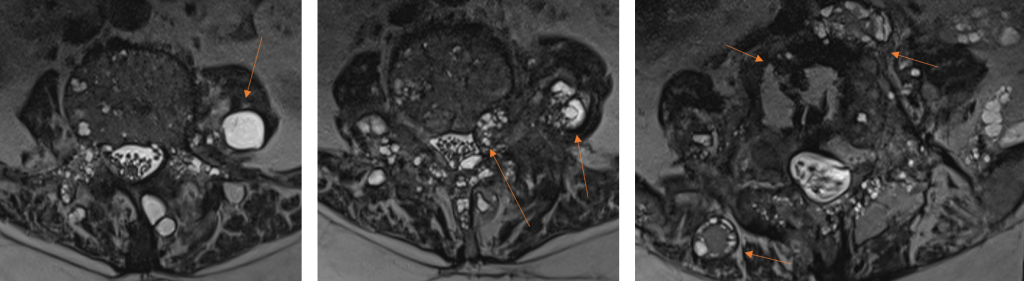

Figura 3: Reconstrucţie în plan oblic-axial din achiziţie 3D în ecou de gradient – ponderaţie T2.

Figura 5: Imagini postcontrast în plan sagital, coronal şi axial. Se remarcă priză de contrast la nivelul pereţilor chistici precum şi la nivelul structurii osoase vertebrale L4 şi L5 din vecinătatea leziunilor chistice (priză de contrast datorată modificărilor edematos-inflamatorii osoase).